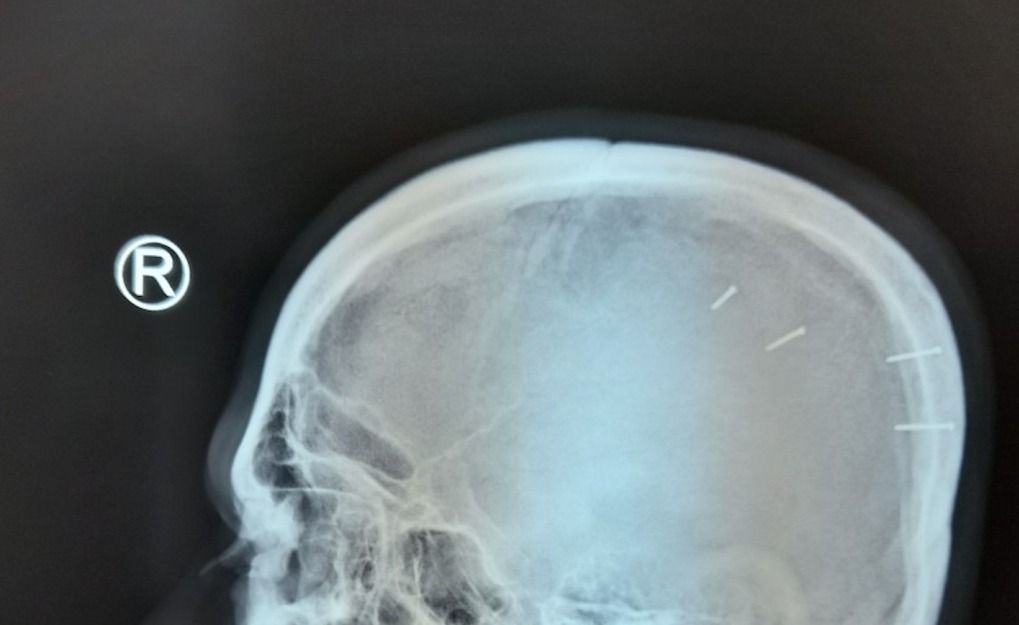

Bệnh nhân 36 tuổi, nhập viện trong tình trạng xuất huyết não, các bác sĩ chụp X-Quang phát hiện 4 cây đinh đóng vào đầu.

Qua khám sàng lọc, ê kíp phát hiện 4 chân đinh vẫn còn trên đầu (dạng bắn máy). Phim X-Quang cho thấy 4 vết thương nhỏ gây ra từ các cây đinh cắm trong hộp sọ.

Phim X-Quang thể hiện 4 cây đinh trong hộp sọ nam bệnh nhân. Ảnh: Thái Hà

Bác sĩ Mạc Đăng Ninh, Khoa Ngoại thần kinh cột sống, cho biết kíp cấp cứu đã phẫu thuật lấy dị vật ra khỏi hộp sọ. Ca mổ khoảng 20 phút do các cây đinh ngắn, chỉ chạm nhẹ đến màng não, không gây xuất huyết não nặng.